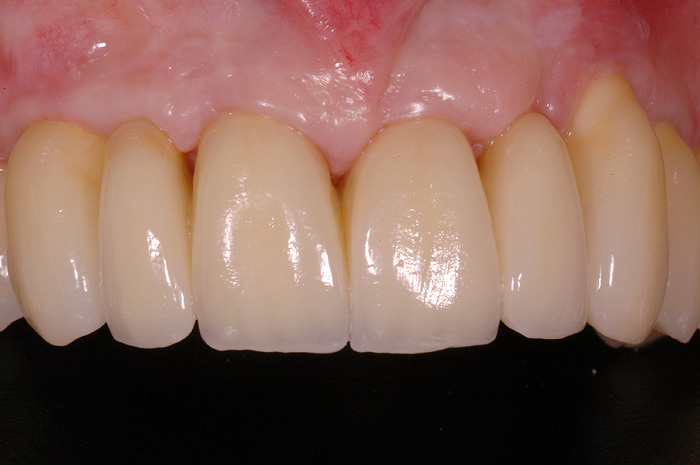

Vollkronen

Ist ein Zahn sehr stark oder bis unter das Zahnfleisch zerstört, kann er nicht mehr mit einer herkömmlichen Kunststofffüllung versorgt werden. Der noch vorhandene Restzahn lässt sich nur noch durch eine Krone restaurieren. Sie besteht aus einem individuell gegossenen Metallgerüst, auf welches in mehreren Schichten Keramik aufgebrannt wird oder kann als rein vollkeramische Krone hergestellt werden, was zu einer noch höheren Ästhetik führt.

Die Restauration eines Zahnes mit einer Krone ist aufwendig. In einem ersten Schritt wird Karies und das alte Füllungsmaterial vollständig entfernt und der Zahnstumpf wieder aufgebaut. Eine präzise Abformung der Situation dient dem Zahntechniker als Grundlage für ein Gipsmodell, auf dem er die Krone herstellt. Sofern Farbe und Form perfekt stimmen, kann die Krone in einer zweiten oder dritten Sitzung beim Zahnarzt zementiert werden. Für die Zeit zwischen Präparation des Zahnes und dem definitiven Zementieren der Krone wird der Zahn mit einem individuell hergestellten Provisorium versorgt.